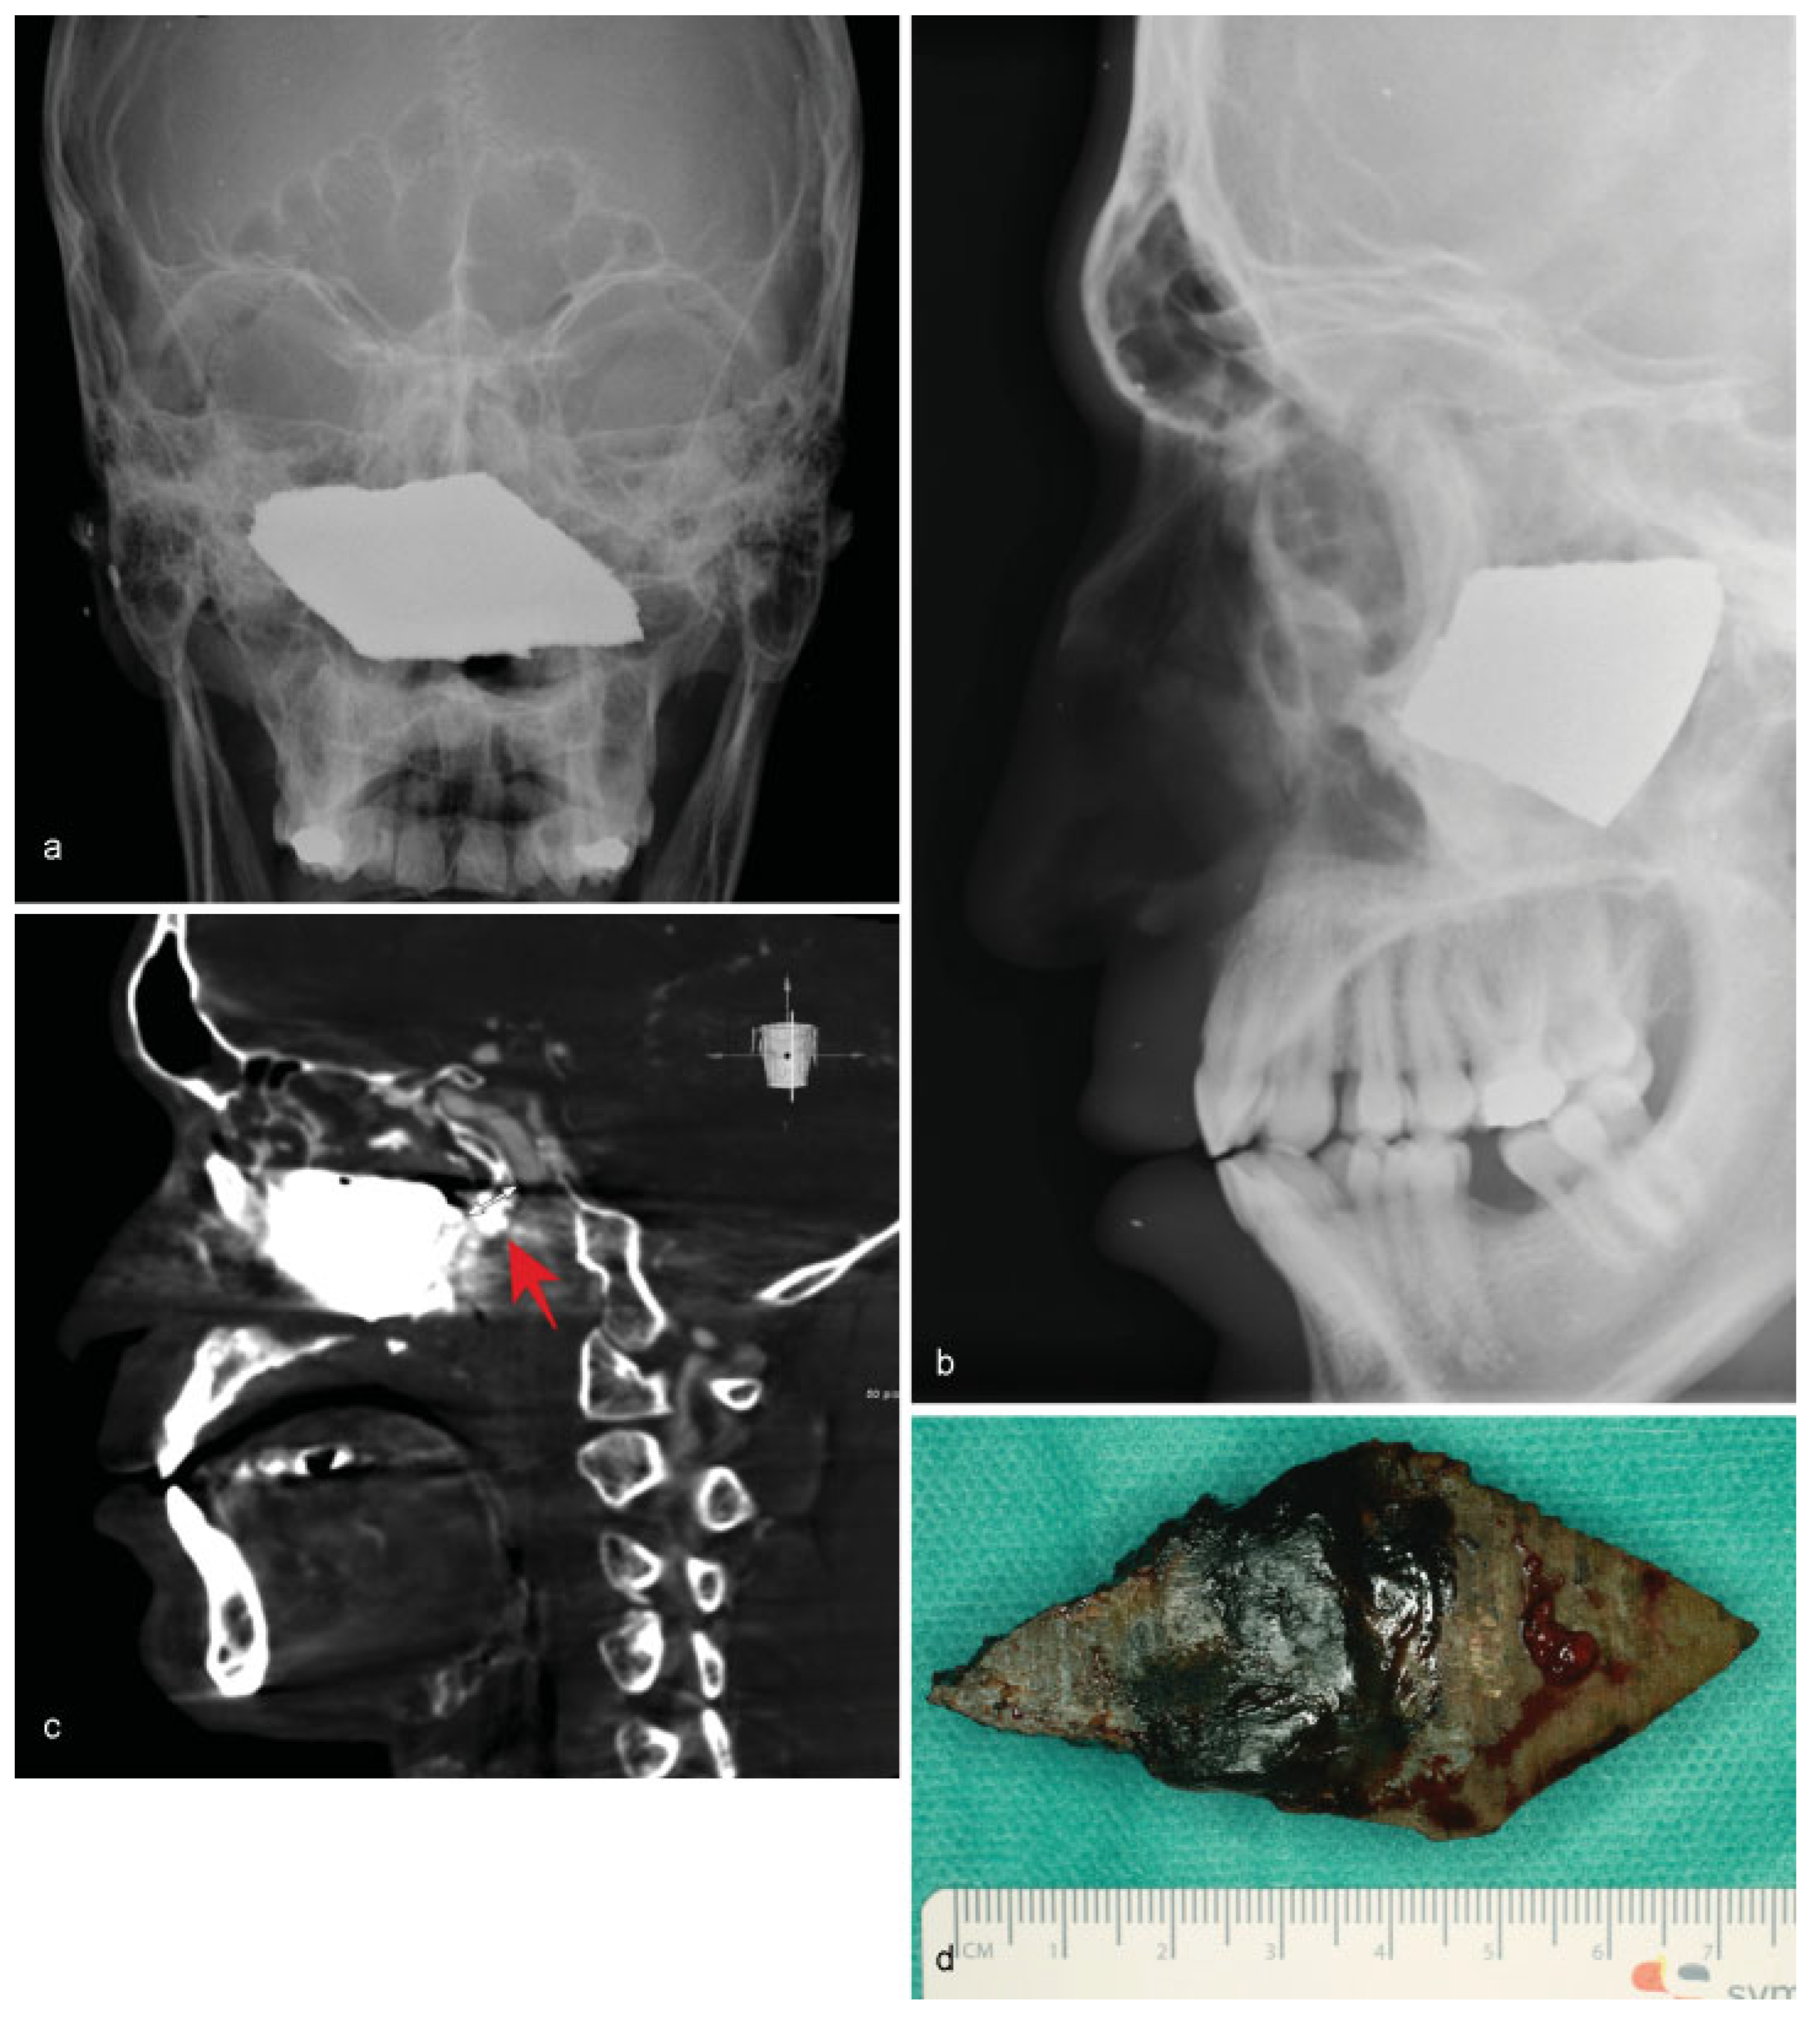

• Case 8: A 22-year-old patient was picked up by an ambulance complaining of facial pain in his right midface. Several months prior, the patient had suffered a blast injury, which caused the loss of his right eye during an armed conflict in Syria, where initial treatment had been performed. Clinically, the patient presented a large scar that extended from his lower right eye to his right nostril. Intranasal examination revealed a purulent foreign object in the nasopharynx. Conventional X-ray followed by an MDCT scan revealed a radiopaque mass in the central midface region, which did not affect the frontobasal region (Figure 8a,b). A cerebral angiogram showed close proximity to the carotid arteries, but without any obvious injury (Figure 8c). Antibiogram revealed multidrug-resistant gram-negative pathogens including Escherichia coli and Pseudomonas aeruginosa. A large piece of shrapnel measuring 8 × 3 × 3.5 cm (Figure 8d) was removed under perioperative antibacterial treatment with endotracheal general anesthesia by performing an incision along the preexisting scar of the cheek and through the existing defect in the maxillary sinus. Following surgical removal, the postoperative outcome included no sequela, and rehabilitation was achieved with ocular prosthesis.

Figure 8. (a,b) Frontal and lateral skull radiographs illustrating a large radiopaque mass in the center of the bony midface. (c) Angiogram showing the close proximity of the foreign body to the internal carotid artery. (d) Postoperative image of the shrapnel.